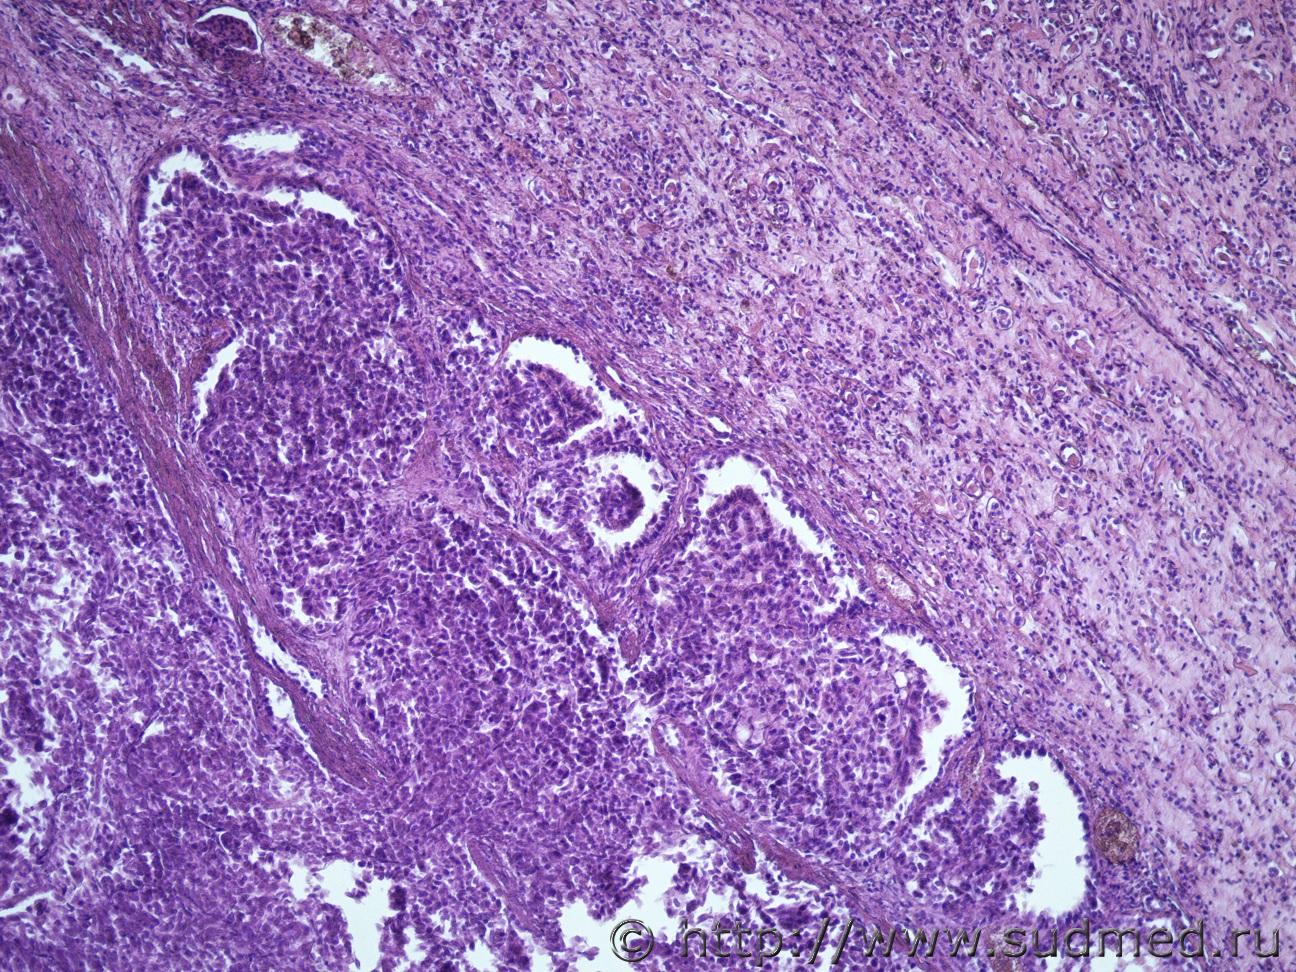

Жен 62 года. На задней поверхности левой почки желтовато-сероватый участок 1на1 см, творожистой консистенции.Судебная медицина - Прикрепленное изображение Судебная медицина - Прикрепленное изображениеСудебная медицина - Прикрепленное изображениеСудебная медицина - Прикрепленное изображениеСудебная медицина - Прикрепленное изображение